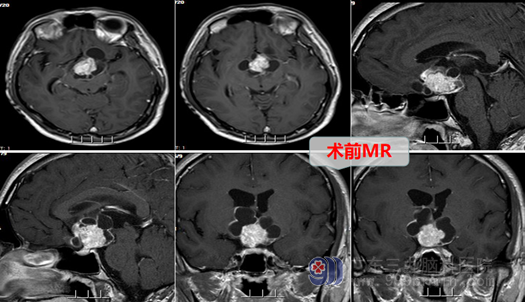

外十科主任欧阳辉教授看了小张拍的检查片子解释道:头部MR显示:鞍上-三脑室底部占位性病变,结合病史,考虑颅咽管瘤可能大,建议补充CT及DWI+ASL+DTI检查。DTI:单体素MRS检查:鞍上-三脑室底部占位性病变感兴趣内表现,仍考虑肿瘤性病变,其余检查结果也都指向诊断为颅咽管瘤。手术指征明确。完善各相关检查后,外十科团队于8月28号在全麻下行内镜扩大经鼻蝶入路颅咽管瘤切除术+颅底重建术+蝶鞍填塞术,手术很顺利,现小张恢复良好,口渴等症状已明显好转,并于近日出院。

影像检查: